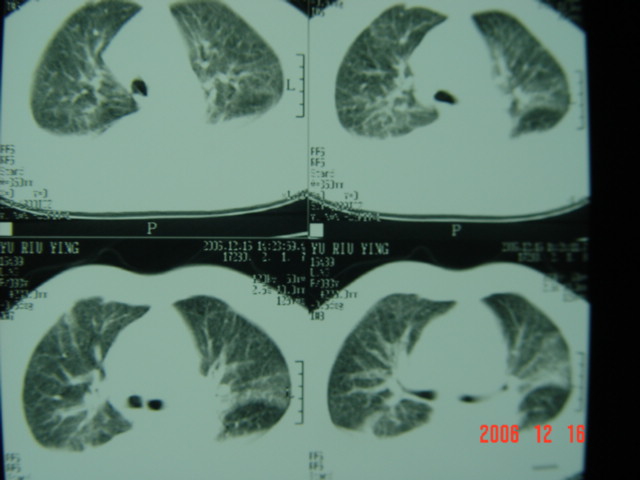

标题: CT5663:女、83岁,轻微咳嗽、左下胸痛。 [打印本页]

标题: CT5663:女、83岁,轻微咳嗽、左下胸痛。

左第八肋腋侧呈膨胀性骨质破坏,内侧见软组织密度肿块。左肺舌段呈楔形实变,基底近胸壁,尖端向肺门。双侧胸壁后缘见新月形水样密度区。

考虑:1、左第8肋骨转移瘤;

2、左肺舌叶肺栓塞可能性大;

3、双侧中量胸腔积液。

考虑:1、左第8肋骨转移瘤;恶性间皮瘤?

考虑1左侧肋骨破坏考虑转移瘤。2左下肺部分肺不张或实变,左肺舌段片团影考虑肺癌可能性大[肺梗塞--往往有明显的胸痛,呼吸急促或困难等表现]。3双侧肺淤血及双侧胸腔积液考虑心功能不全所致可能性大